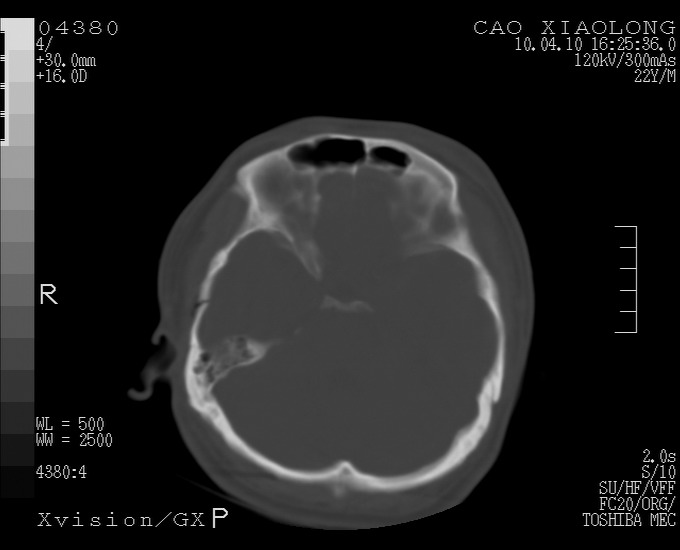

以下是引用随光逐影在2010-4-11 11:00:00的发言:[br]1)左侧额颞顶部硬膜下血肿。2)蛛网膜下腔出血。3)右侧颞顶部颅骨线形骨折。[br][br]20小时后复查:左侧额颞叶脑挫裂伤;左侧额颞顶部硬膜下血肿及蛛网膜下腔出血有吸收表现;右侧颞顶部颅骨线形骨折。[br]